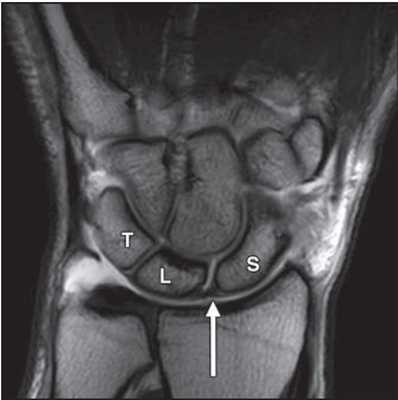

МРТ кисти. Корональная Т1-взвешенная МРТ. Нормальное изображение ладьевидно-полулунной связки. Обозначения: S - ладьевидная кость (scaphoid), L - полулунная кость (lunatum), T- трехгранная кость (triquetrum).